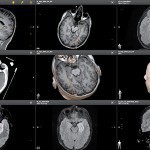

Die Visualase-Therapie ist ein innovatives Verfahren, das mithilfe eines präzisen Lasersystems von Medtronic erkranktes Gewebe im Gehirn gezielt behandelt. Durch einen minimal-invasiven Eingriff wird eine winzige Laserfaser in das Gehirn eingeführt, um das betroffene Gewebe zu erhitzen und zu zerstören. Die Behandlung erfolgt unter Echtzeit-MRT-Bildführung, wodurch eine hohe Präzision und Sicherheit gewährleistet werden.

Im Zuge der Vorbereitung der Visualase-Laserablation werden kernspintomographische Aufnahmen des Gehirns des Patienten oder der Patientin angefertigt, computergestützt bearbeitet und am virtuellen 3D-Modell der Eingriff geplant. Anhand dieser Darstellung legen Epilepsie-Spezialist Prof. Dr. Christian Elger und der erfahrene Neurochirurg und Operateur Prof. Dr. med. Thomas Gasser im stereotaktischen Verfahren den genauen Zielpunkt für die Laserablation fest.

- Die Person liegt hierbei im MRT, dessen Bilder in Echtzeit auf die mobile Kontrollstation übertragen werden. Von dort aus beobachten die Experten die Ebenen im Gehirn, durch die der Katheter bis hin zur zu behandelnden Stelle geführt wurde, und überwachen die Thermoablation.

„Mit unserer erstklassigen Bildgebung im 3 Tesla MRT und Videodoppelbilder- und EEG-Ableitungen haben wir vor dem Eingriff das epileptisch aktive Areal im Gehirn des Patienten genau lokalisiert und räumlich definiert.“

– Prof. Dr. Thomas Gasser